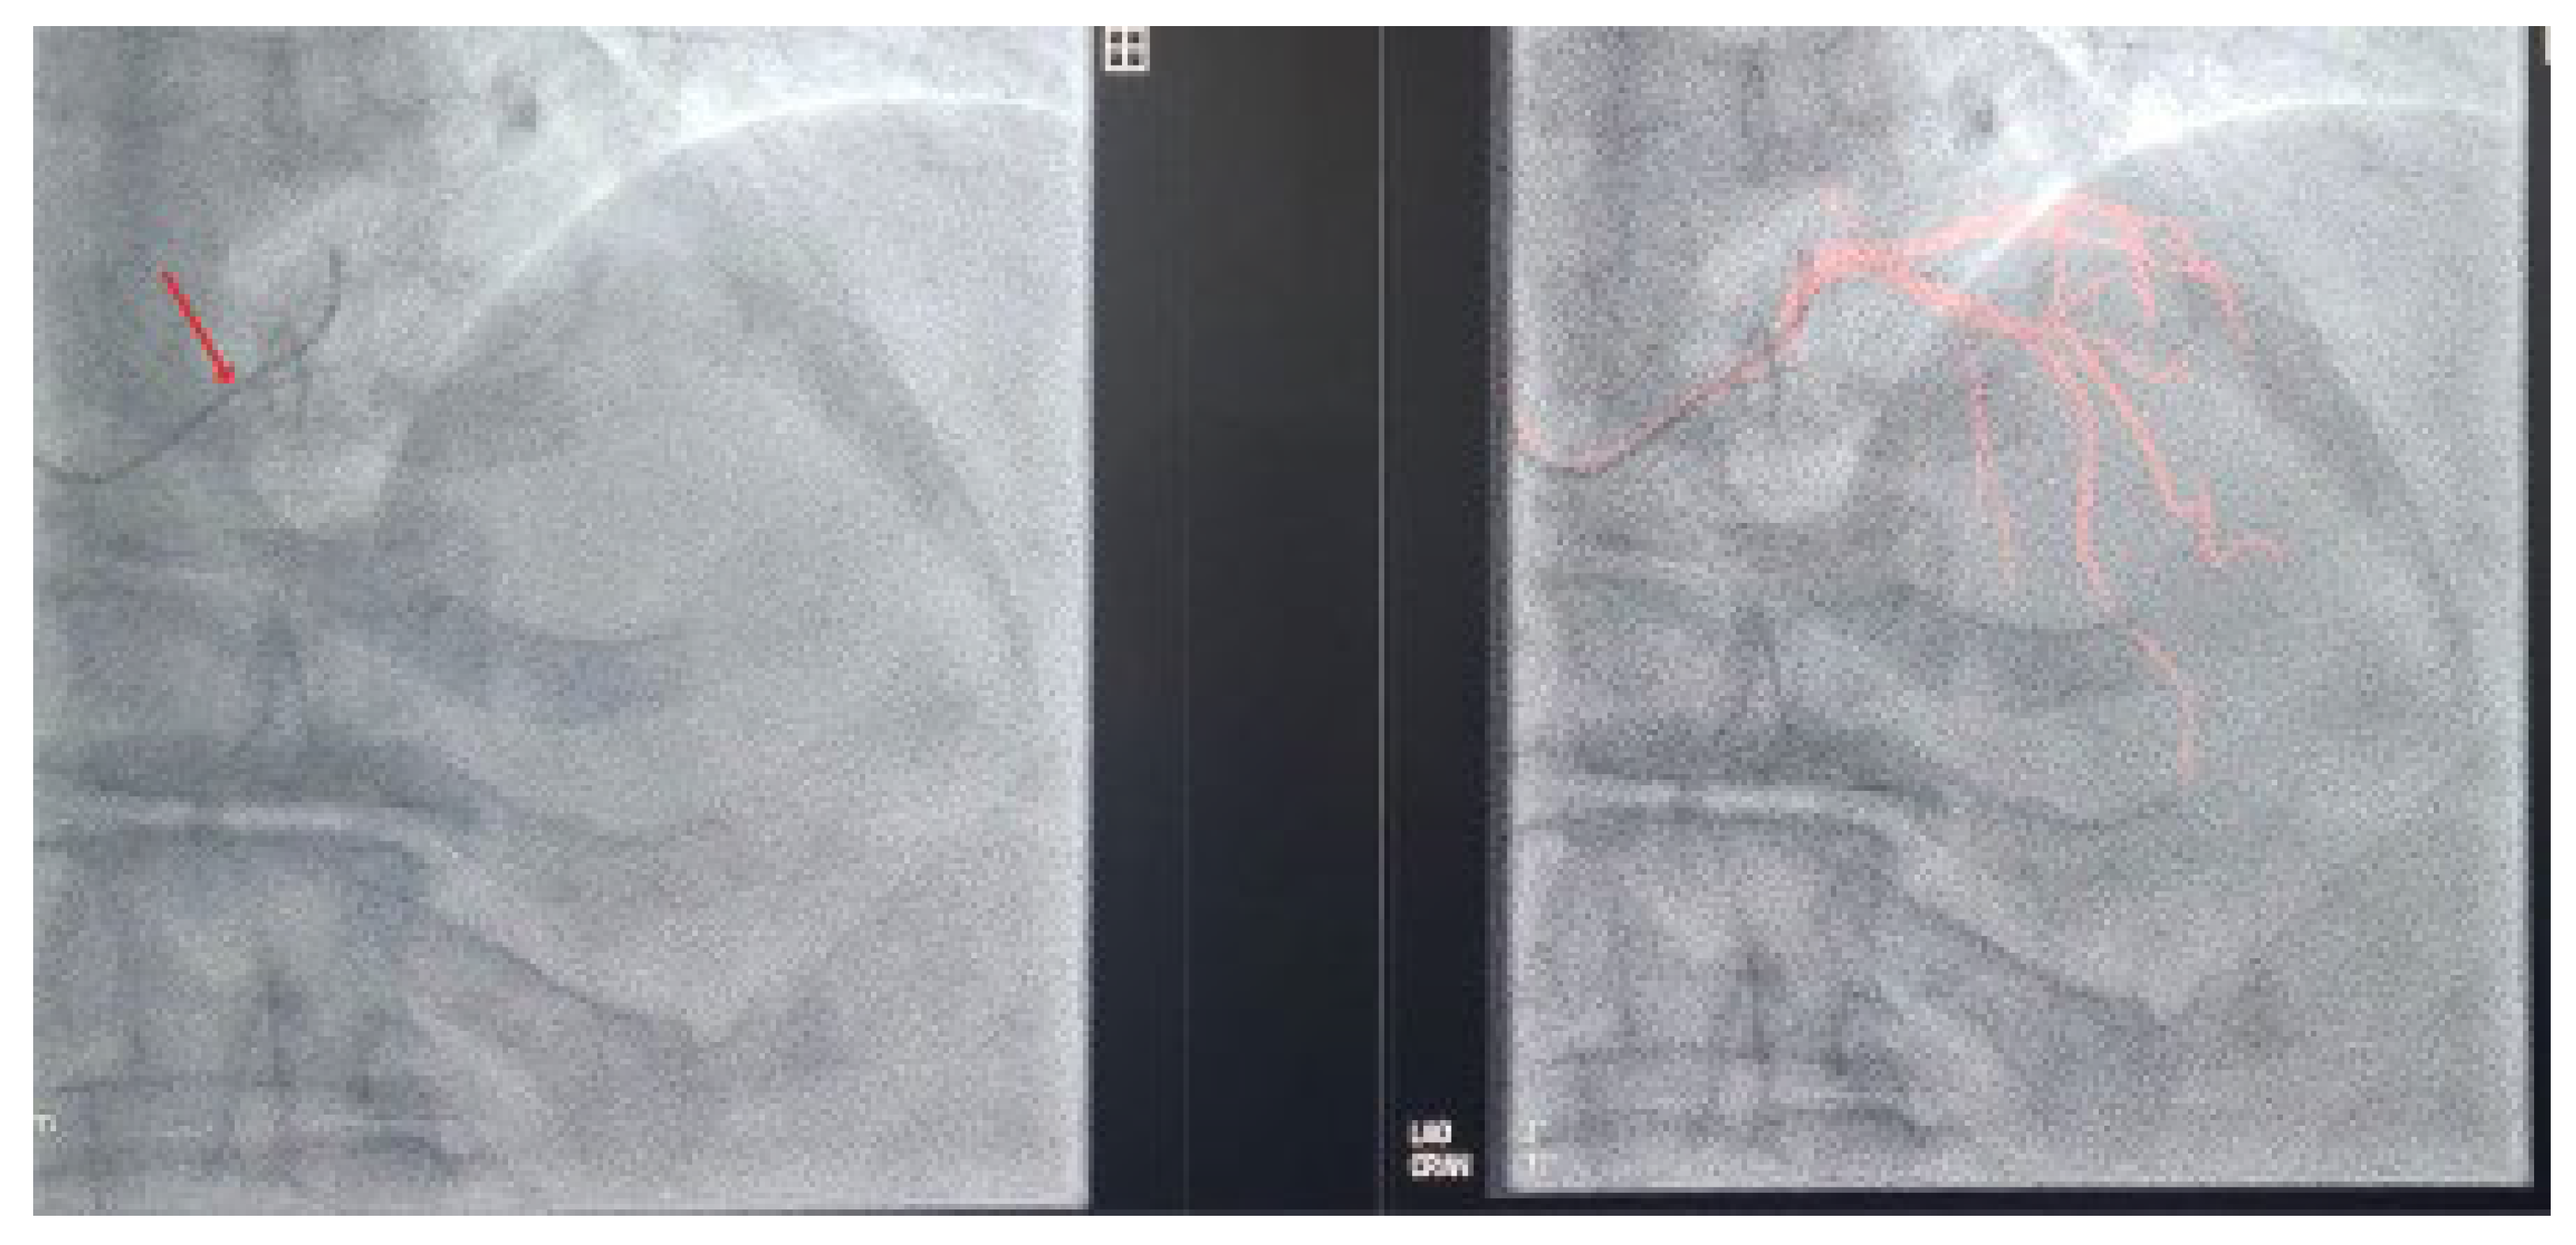

To address these challenges, adjunctive imaging modalities have been adapted to enable ultra-low contrast PCI. Intravascular ultrasound (IVUS) provides detailed cross-sectional images without reliance on contrast media (Figure 1) and is recommended in complex interventions [5,6]. OCT provides high-resolution plaque characterisation and stent assessment (Figure 2), but requires flushing, typically with contrast media; however, substitutes such as low-molecular-weight dextran and heparinised saline have shown promise as alternatives [51,52,53,54]. DCR software overlays a live coronary roadmap onto the fluoroscopic image, enabling navigation of coronary tools and stent delivery without repeated contrast injections (Figure 3) [7,55]. While these modalities provide valuable anatomical information, they remain dependent on fluoroscopic platforms and do not eliminate contrast use entirely, highlighting the potential role for complementary navigation technologies such as EAMS.

Figure 3. JL 3.5 coronary catheter (arrow) positioned in the left coronary cusp in LAO cranial view following coronary angiography (left). DCR map visualising the coronary tree without contrast injection (right).